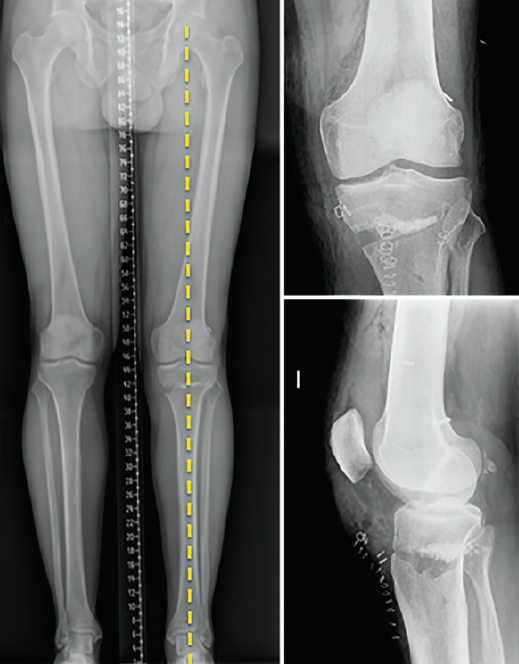

Other tests that contribute to the diagnosis are stress valgus radiographs (local anesthesia infiltration is advised in order not to underestimate the test), magnetic resonance imaging (MRI) and arthroscopic exploration (Figure 1).

Figure 1. Arthroscopic view through the anterolateral port of a positive drive-through sign with abnormal aperture of the internal compartment secondary to insufficiency of the medial collateral ligament. Right knee.